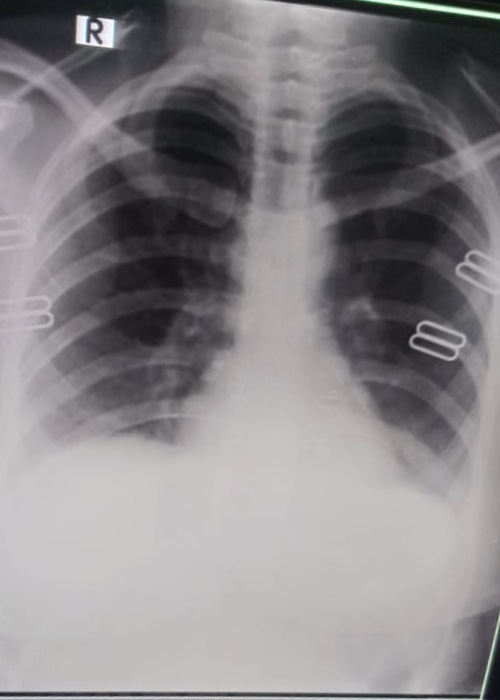

My brother is covid positive. He is diabetic too. He is having sore throat and body ache now. The attached photo is his chest X-ray. Can you please tell what’s his state now.

Chest d rat show inflamation in lungs consult online for detailed assessment